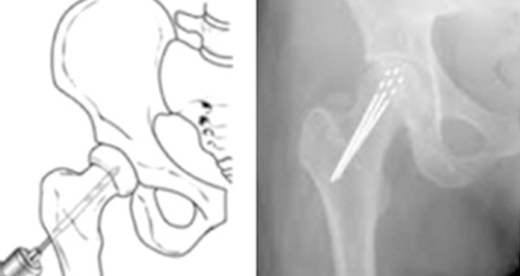

대퇴골두 중심 감압술

대퇴골두에 구멍을 뚫어 벼의 압력을 줄이고, 새로운 혈관을 형성시켜 영양을 공급하는 수술입니다.